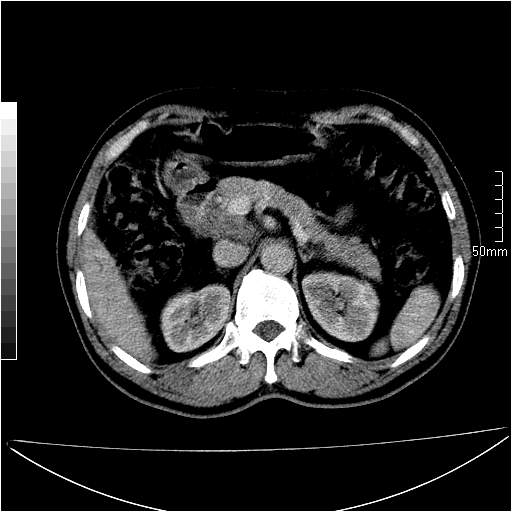

男性,54岁,皮肤黄染,搔痒一周余.b超示肝左叶回声异常.初步诊断1胆总管下段结石2胆囊结石伴慢性胆囊炎请各位战友帮忙看一下肝脏多发低密度如何解释恰当.增强效果不是很好.请大家见谅.

胆总管及肝内胆管扩张,考虑是结石!但,肝内的低密度区增强不明,可能是肝ca,因为肝ca在增强时呈快进快出.另年胆总管扩张原因,可以考虑一下是不是,胆管ca.再次要考虑肝内的低密度是否为海绵状血管瘤所致!

首先,胆总管下端结石梗阻伴肝内胆管扩张可确定。

其次,增强动脉期肝静脉显影,肝实质密度不均。——此为右心功能不全引起肝淤血的表现。

另外,肝八段低密度占位,呈多灶性,考虑肝脓肿或肝癌可能,(图像质量欠佳)建议进一步检查。

由于胆囊窝内结构显示不清,肝脏病灶又邻近胆囊窝首先考虑胆囊癌肝受侵犯。而后因肝脏病灶强化有渐进改变,且相邻胆管扩张,故考虑肝胆管细胞癌待排。

左肝胆管细胞癌。

胆总管下端结石。